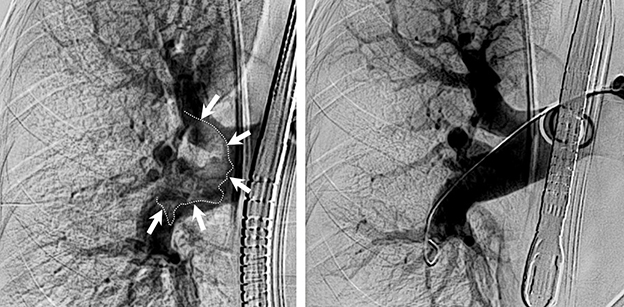

Erstmalig in Österreich und erst das vierte Mal in Europa, wurde bei einer Patientin am 19. März an der Innsbrucker Univ.-Klinik für Radiologie, eine Lungenembolie mit einem völlig neuartigen mechanischen System entfernt. Der Patientin geht es gut, sie liegt mittlerweile auf der Normalstation.

„Bei dem kürzlich angewandten System wird ein relativ dicker Schlauch über einen Schnitt in der Leiste, durch ein großes Blutgefäß und das Herz bis in die Lunge vorgeschoben und das Gerinnsel restlos abgesaugt“, erklärt Martin Freund, Geschäftsführender Oberarzt an der Radiologie. „Es ist auch für uns beeindruckend, wie schnell bei diesem Eingriff ein Erfolg zu sehen ist“, sagt Alexander Loizides, Oberarzt an der Radiologie, der den Eingriff gemeinsam mit Freund durchgeführt hat. „Die Werte der Patientin verbesserten sich in der Sekunde in der das Gerinnsel abgesaugt war.“

Die größte Neuerung bei diesem System ist das große Volumen des Schlauches. Bisherige Systeme zur manuellen Entfernung von Blutgerinnseln in der Lunge sind nur ein Drittel so dick und hätten im aktuellen Fall nicht zum Erfolg geführt.

Im Bild: Lunge mit großem Blutgerinnsel (markiert) und dementsprechend mangelnder Durchblutung (links) und nach Entfernung des Gerinnsels und guter Durchblutung (rechts).